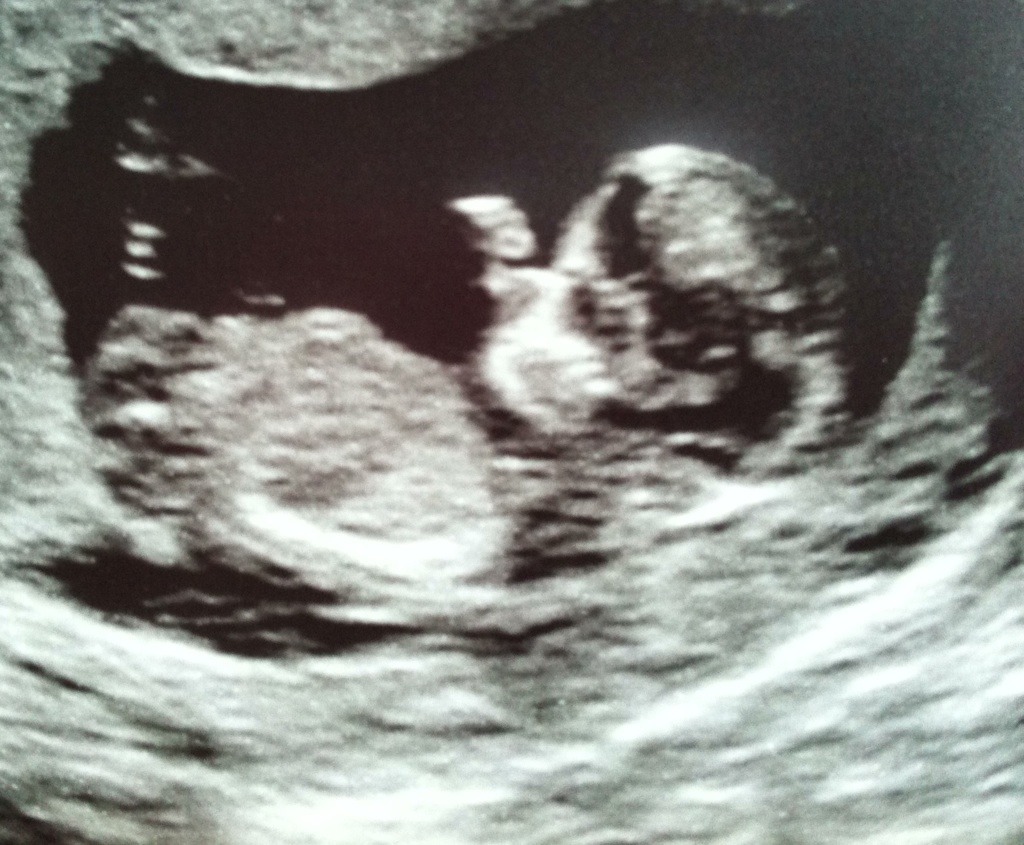

No nub, scull looks :xy:

I don't see a nub, the skull looks boyish

Cant tell, but very cute profile.